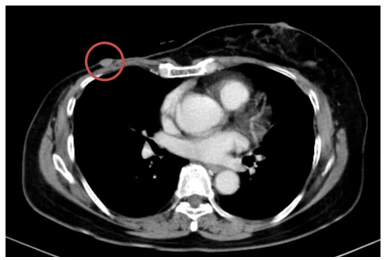

-  Chụp cắt lớp vi tính bụng: Theo dõi dày khu trú tuyến thượng thận trái tạo nốt đường kính khoảng 9mm

Hình 3. Hình ảnh chụp CT bụng trước điều trị: Nốt tuyến thượng thận trái